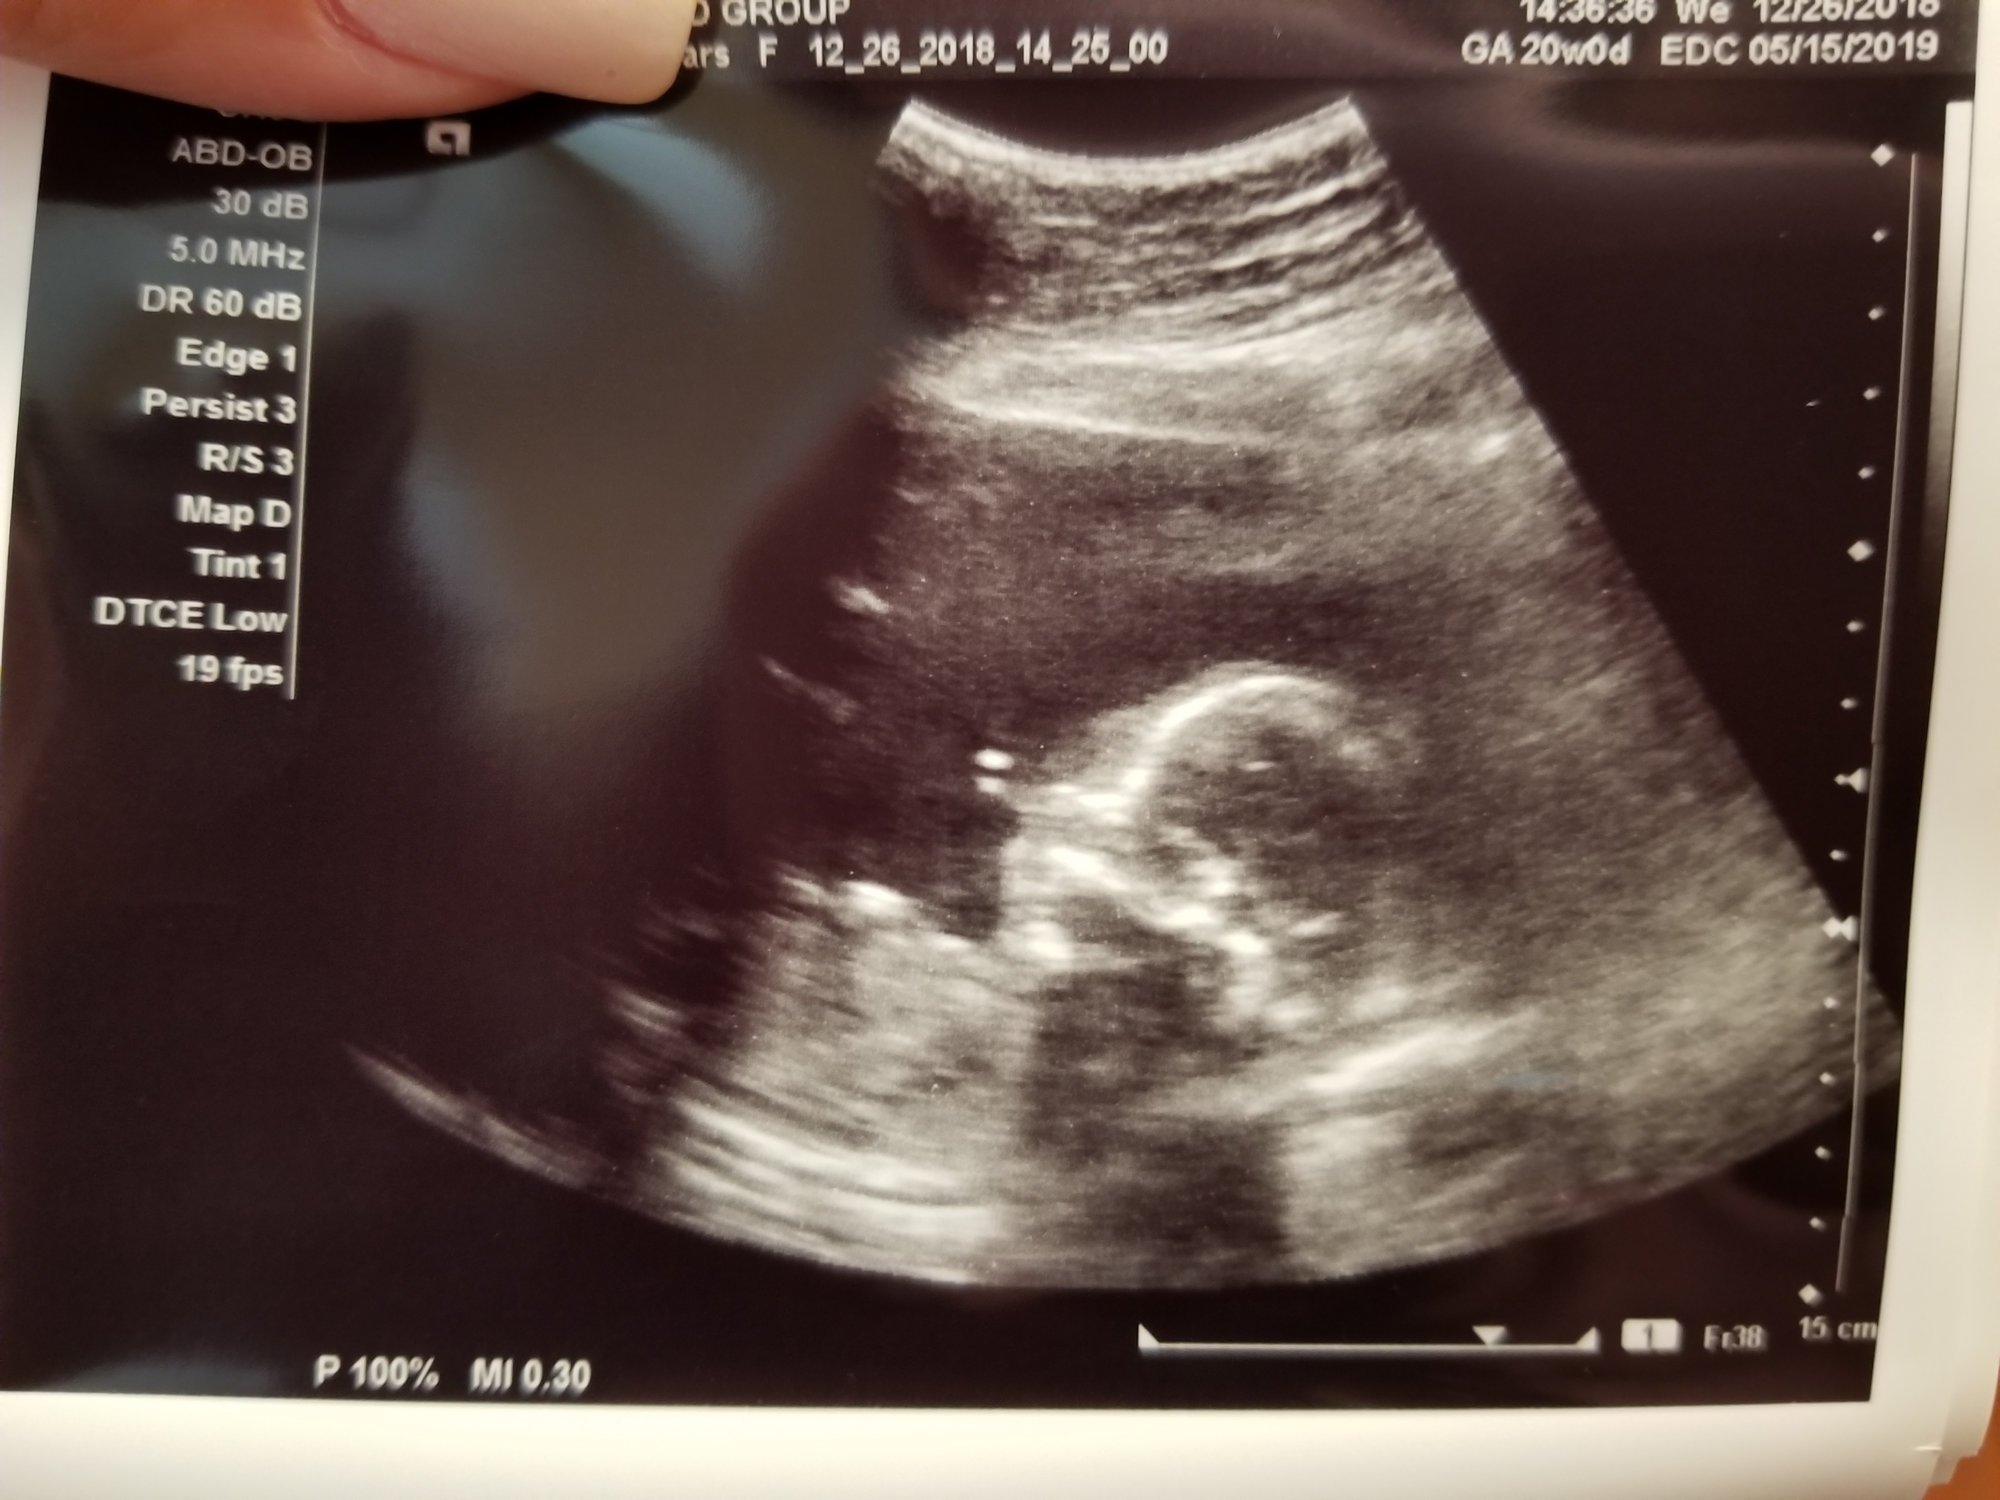

Baby #3. I had my anatomy scan on Jan 2 with the maternal fetal medicine doctor. He's currently breech and facing my spine. The scan took a while, but all looked good enough to cancel my consultation with the doctor afterward. Due to age, and other risk factors, I go back in for another ultrasound in 4 weeks to check growth.